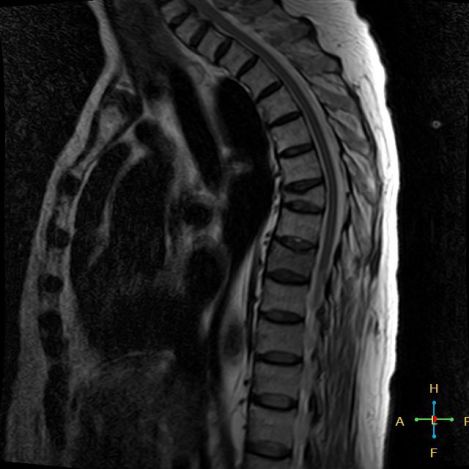

2 良性压缩性骨折 椎体形态:楔形、凹陷形。 椎体连续性病变(骨质疏松):新鲜、陈旧骨折并存。

椎间盘改变:椎间盘增厚呈双凸透镜状, 椎间盘疝入椎体, 形成许莫氏结节。

椎体后上角或后下角向后翘起, 呈尖突样突入椎管, 具有特异性,为其它原因的骨折所少见。

——良性压缩性骨折MR信号特点—— 良性骨折的修复过程:缺血性变化--修复(骨髓水肿、血流增加或充血现象)--修复近完成(血流恢复正常)--慢性期(脂肪组织再生)。 正常成人:椎体为黄骨髓,T1WI 、T2WI 均为高信号。 当骨髓内出现水肿时,T1 低信号, 与残余的正常骨髓形成明显对比,所以椎体压缩骨折后,MR 信号改变以 T1WI 上观察最好;而在常规 T2WI 图像上,病变骨髓的长 T2 高信号与正常骨髓脂肪信号差别较小,不易观察;T2WI 脂肪抑制技术对于突出显示骨折区长 T2 组织信号具有独特优势,对于判断椎体是否发生脂肪变及骨折是否愈合也有一定价值。 急性早期,椎体压缩,局部缺血,骨髓水肿,T1WI 不均匀低信号,T2WI 高信号,增强扫描无明显的强化。 随后,骨折部位开始修复,血流量增加,增强扫描可出现明显的强化,平扫信号无改变。 慢性期,骨髓内脂肪组织再生,T1WI 椎体内呈混杂高信号。

由于大多数外力轻微,椎体内多形成范围局限、移位不明显的骨折线,骨折线周围水肿亦多局限,因此,较少出现全椎体信号异常。

椎体后角回避现象:T1WI 椎体上部或大部呈低信号, 而后角信号不变。